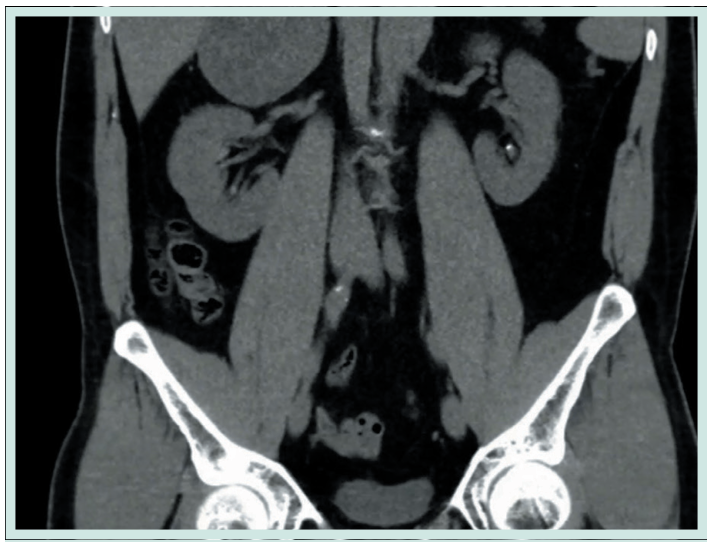

Se realizaron estudios metabólicos y hormonales, los cuales fueron negativos, confirmando la ausencia de actividad secretora. Se indicó manejo conservador y seguimiento con imágenes periódicas. A los dos años de seguimiento, una urotomografía contrastada endovenosa mostró una masa suprarrenal derecha de

7.5 × 6 cm, con 68 unidades Hounsfield (UH) en fase de contraste que evidenció crecimiento de la lesión. Ante el aumento significativo de tamaño y la sospecha de transformación tumoral, se decidió tratamiento quirúrgico, realizándose una adrenalectomía derecha. La evolución postoperatoria fue satisfactoria, sin complicaciones.

Lesión sólida bien delimitada en la glándula suprarrenal derecha de aprox. 7.5 x 6 cm con realce heterogéneo tras la administración de contraste, con zonas hipodensas compatibles con necrosis (flecha roja).